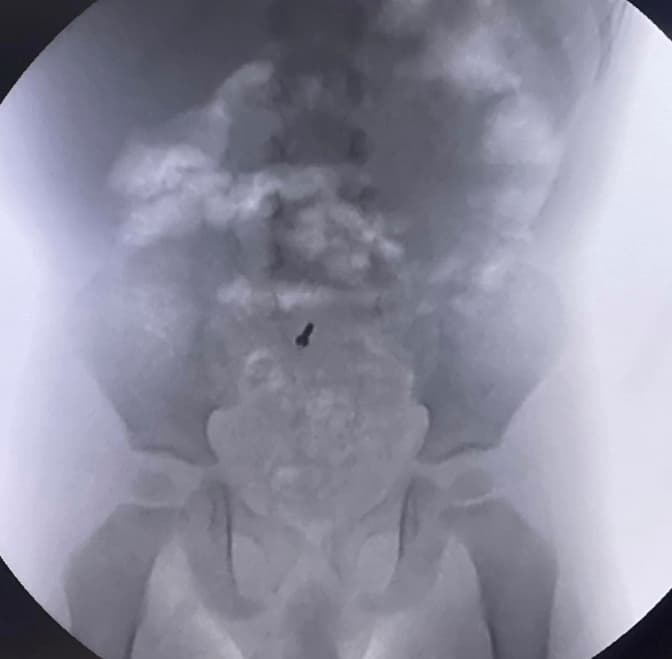

Данилку з Івано-Франківська по стану здоров’я потрібно було зробити рентгенографію і під час діагностичного дослідження лікарі випадково виявили металевий шуруп у його черевній порожнині. Медики разом із батьками вирішили спостерігати і сподівалися, що шуруп вийде самостійно. При повторних рентген-дослідженнях, шуруп залишався на місці. Хірурги вирішили провести діагностичну лапароскопію, перевірили весь кишківник і знайшли шуруп в апендиксі, що буває вкрай рідко. Після знахідки одразу видалили його.